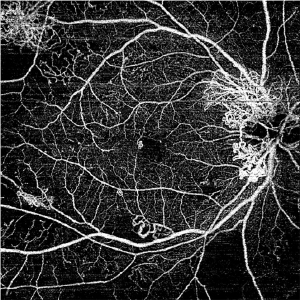

トプコン トリトン

3次元眼底像撮影装置

主な特徴

・スキャン光が見えない、中心波長1,050nmのSSOCT

・100,000Aスキャン/秒

・マルチモダルOCT(カラー眼底/レッドフリー/OCT/FA/FAF/OCT-A/前眼部撮影)

・SS OCT Angiography、広角パノラマOCT-A撮影

当緑内障疾患や網膜疾患など幅広い眼疾患の早期発見や病状の分析にかかせない検査機器です。

精細な画像診断が可能なので網膜の微細な病変も見逃しません。

症例ごとにいろいろなレポートを作成することにより医師が診断においても具体的になり診察で前回との症状の違いなどの説明がスムーズです。